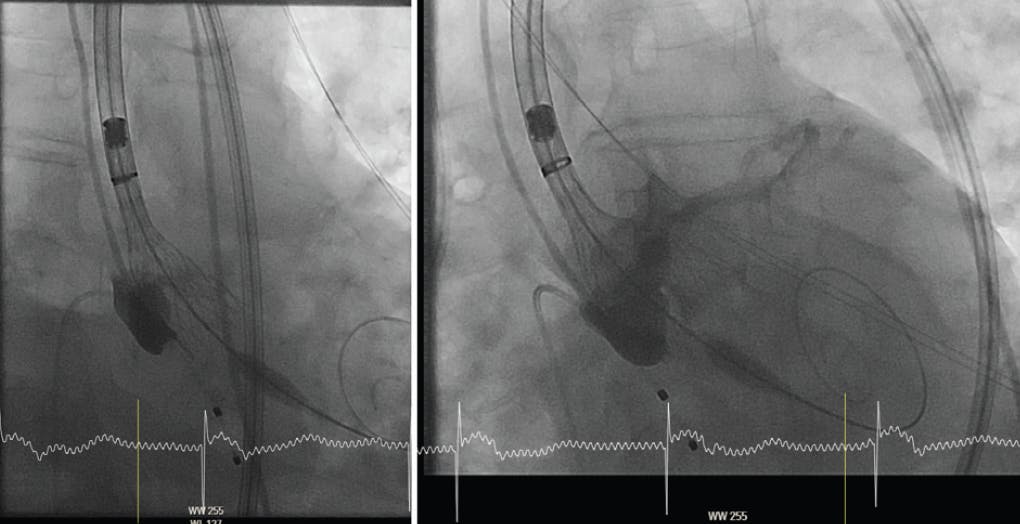

To start, a regular three-cusp coplanar view should be obtained from a high-quality, gated CT with contrast. Rotation along the S-curve allows for overlap of the left and right coronary cusps, leading to isolation of the noncoronary cusp (Figure 1). In this so-called cusp overlap view, for the operator the LVOT is elongated and the parallax in the markerband reduced—or removed in most cases.

Figure 1. Illustration and CT-based aortography of the coplanar three-cusp view (left side) and the cusp overlap view (right side). In the cusp overlap view, the operator gets a “two-cusp” view, with the isolated noncoronary cusp at one side and the overlapped left coronary cusp and right coronary cusp on the other side.